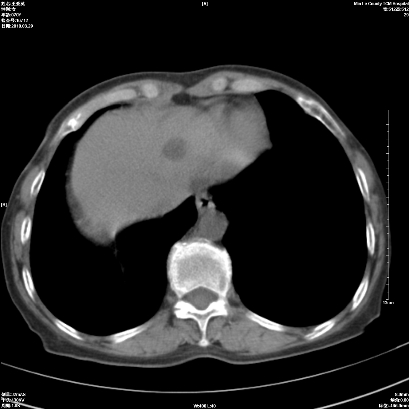

1 右肺门占位伴上叶不张 2 有肺多发感染 3 肝脏转移? 建议增强

1、右侧中央型肺癌伴右肺上叶不张建议支气管镜检   2、右肺中叶及下叶陈旧性病灶   3、肝内多发低密度影,肝内多发转移不除外,建议ct增强!

肝脏多发占位建议增强检查

1)考虑右肺中央型肺癌伴右肺上叶肺不张,右肺门淋巴结转移;建议行支纤维镜检查。2)右肺中叶、下叶及左肺上叶舌段感染性病变。3)肝内多发低密度影,不排除转移瘤可能;建议行ct增强扫描检查。